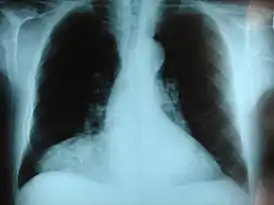

![]() Фронтальный рентгеновский снимок грыжи Моргани. | |

- ретрокостостернальные (справа — треугольника Морганьи, слева — Ларрея)